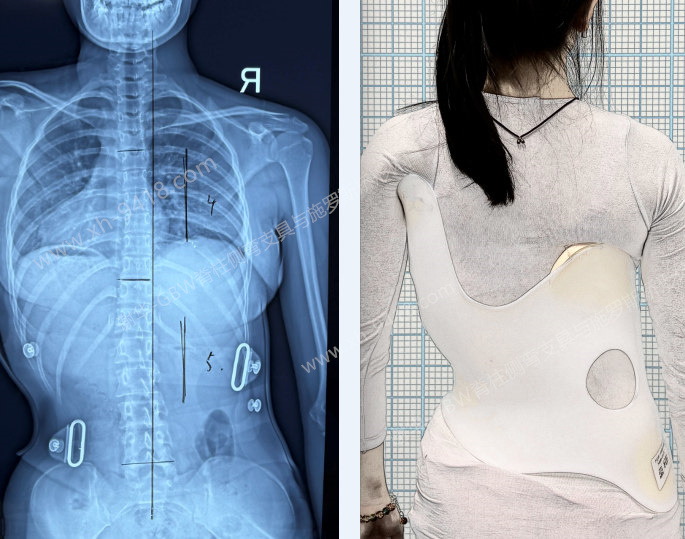

蒋X,女,13岁时发现脊柱侧弯。初诊时为典型的“S形”曲线,Cobb角为胸弯22°,腰弯32°,剃刀背分别为胸7°、腰8°;当时Risser征为2级,且初潮仅半年,根据青春期女孩生长发育规律,未来存在明显加重的风险。建议家长为孩子配置GBW型支具,并结合施罗斯体系的体操训练进行系统矫正。

支具穿戴情况-针对S形曲线的GBW-4C型支具

经过2年多的坚持佩戴与训练,孩子的弯度逐渐得到控制和改善。近日在16岁复查时,胸弯为15°,腰弯14°,整体保持为轻度的对称性S形曲线。体表外观也明显改善,站立位时躯干对称性良好,剃刀背降至5°以下,回到正常范围。